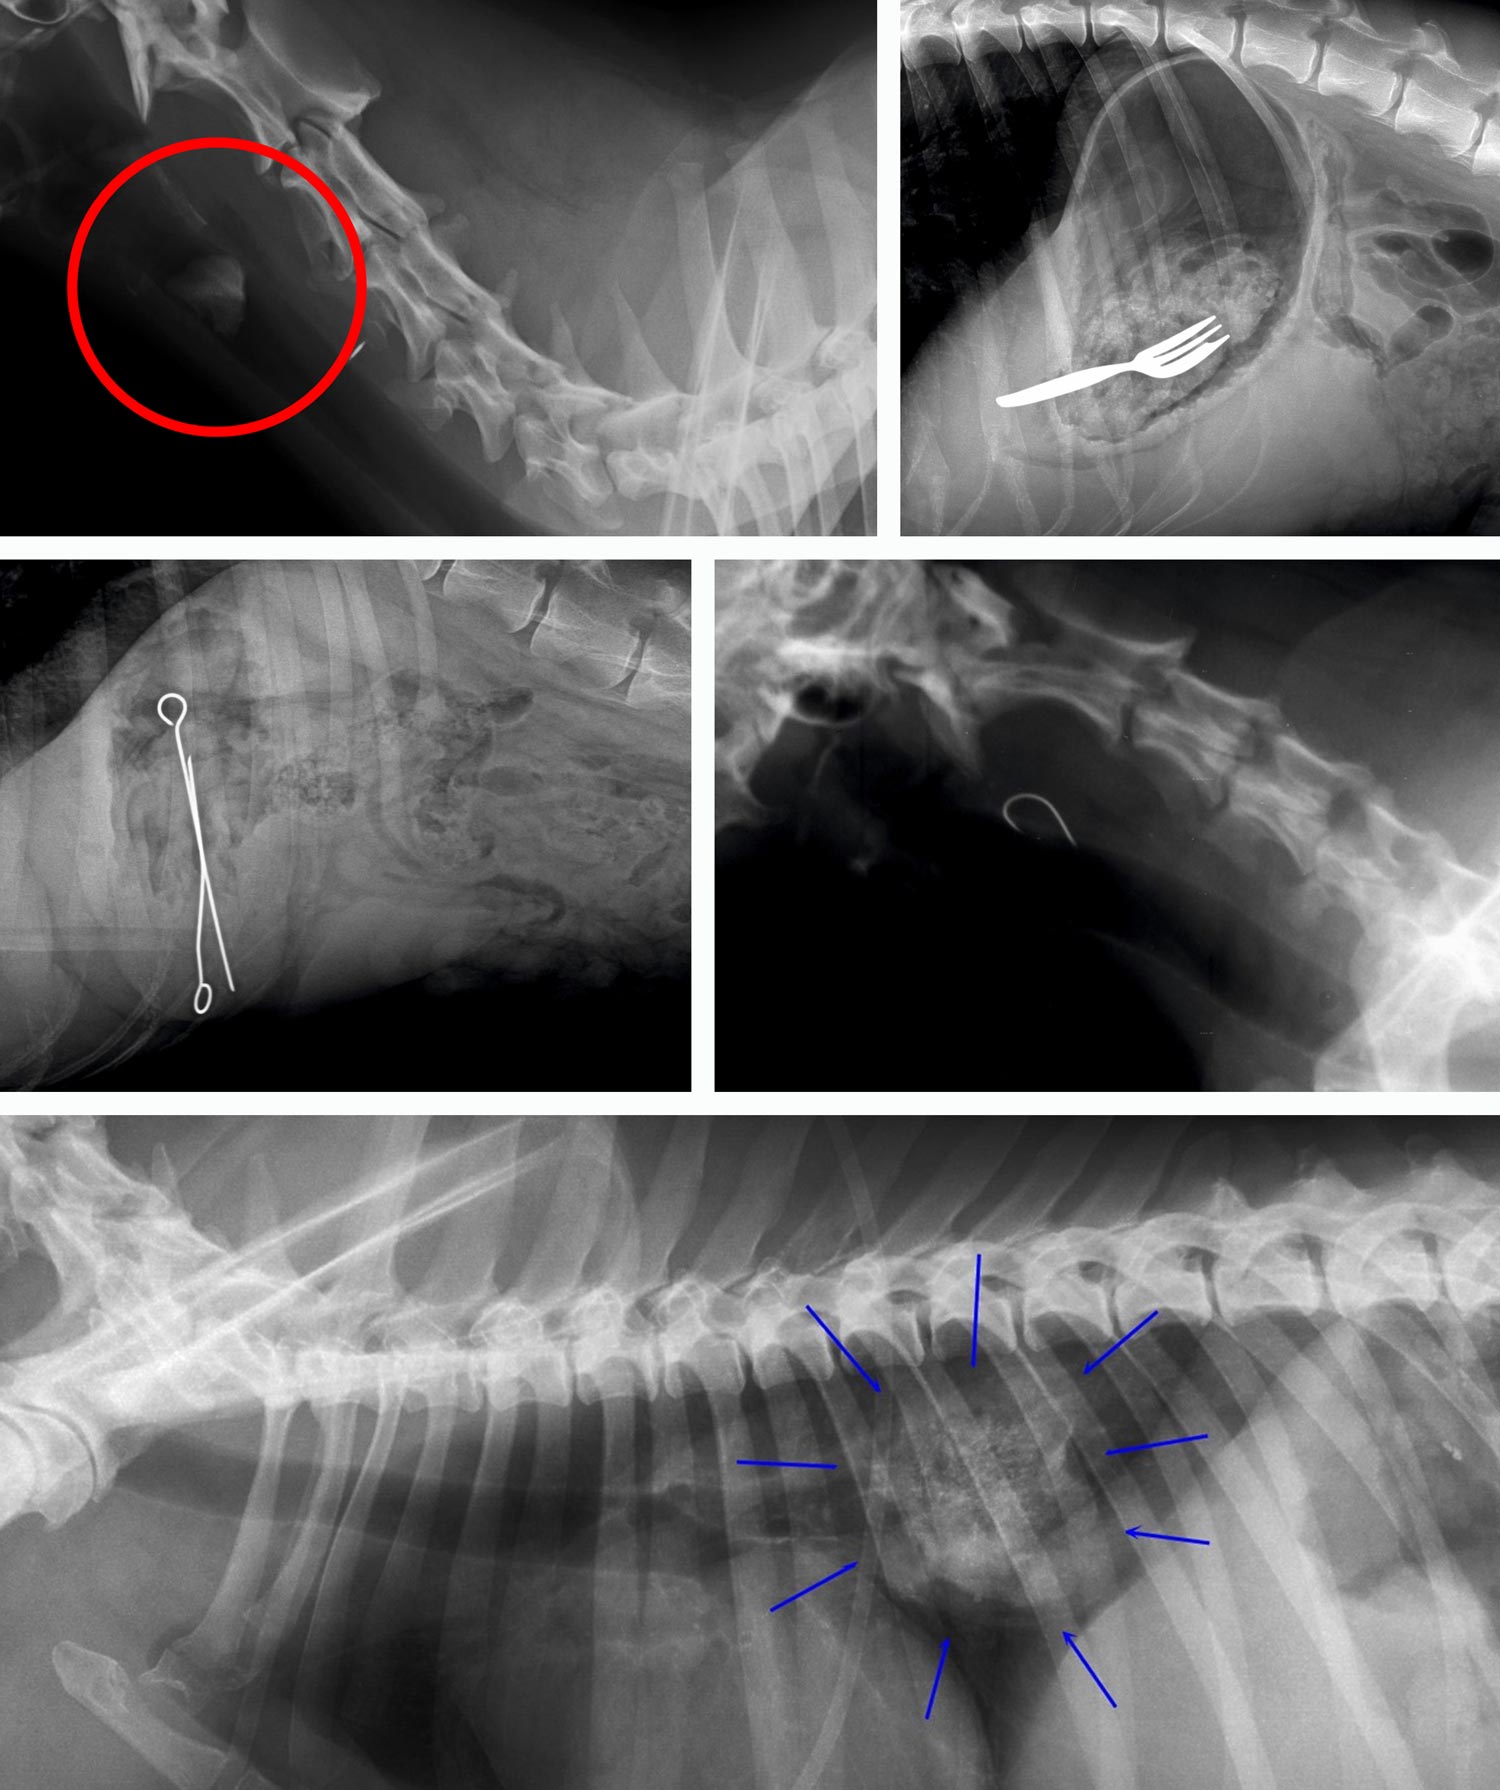

Einblicke ins Verborgene – Fremdkörper im Verdauungstrakt

Auf diesen Röntgenaufnahmen sehen Sie Beispiele von Fremdkörpern, die Tiere verschluckt haben. Von Spielzeugteilen bis hin zu ungewöhnlichen Objekten – solche Fälle begegnen uns in der Tiermedizin regelmäßig. Dank moderner Endoskopie-Technik können wir viele dieser Fremdkörper schonend und ohne größere Operation entfernen. Sollte Ihr Tier Symptome wie Erbrechen, Appetitlosigkeit oder Unwohlsein zeigen, zögern Sie nicht, uns zu kontaktieren.